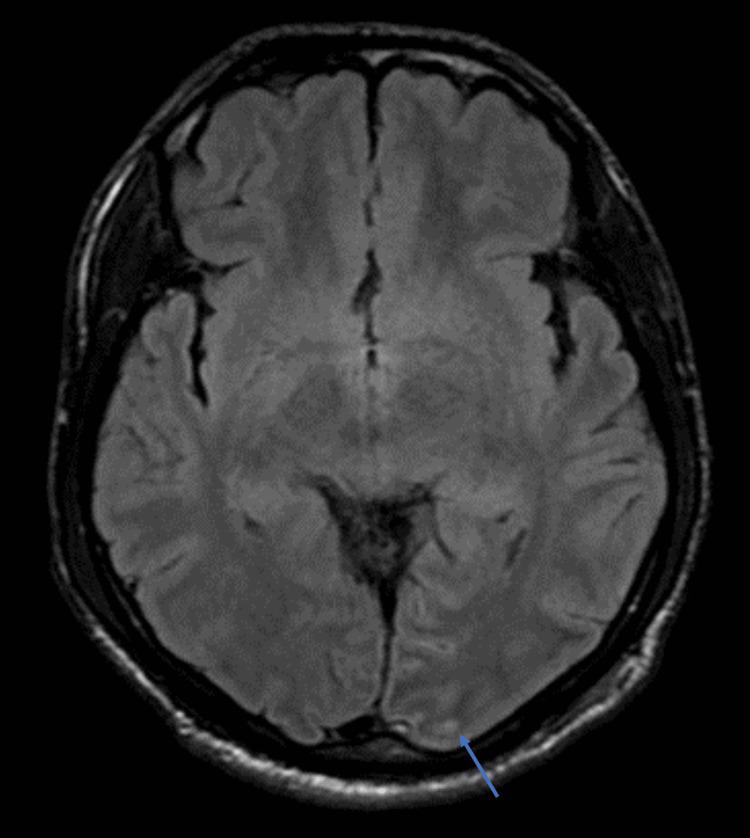

Melioidosis is caused by a Gram-negative, facultative intracellular bacterium. Because melioidosis can mimic many diseases, it requires more advanced laboratory facilities with the necessary expertise and can become an underdiagnosed yet serious infection with high mortality and morbidityOur patient is a middle-aged male with new-onset uncontrolled type 2 diabetes mellitus who presented with high-grade fever, productive cough and altered mental status. CT thorax showed diffuse middle and lower zone consolidation while MRI brain noted meningitis with cerebritis. Blood culture grew. The patient was started on meropenem for melioidosis, however, no adequate improvement was seen. In view of this inadequate response, parenteral cotrimoxazole was added. Significant improvement was noted and cotrimoxazole was continued for six months.

类鼻疽病由革兰氏阴性兼性胞内细菌引起。由于类鼻疽病可模仿多种疾病,它需要更先进的实验室设施以及具备必要专业知识的人员,并且可能成为一种诊断不足但严重的感染,具有高死亡率和发病率。我们的患者是一名中年男性,患有新发且未得到控制的2型糖尿病,出现高热、咳痰和精神状态改变。胸部CT显示中、下肺野弥漫性实变,而脑部MRI提示脑膜炎合并脑炎。血培养有细菌生长。患者开始使用美罗培南治疗类鼻疽病,但未见充分改善。鉴于反应不佳,加用了胃肠外复方新诺明。患者有显著改善,复方新诺明持续使用了6个月。